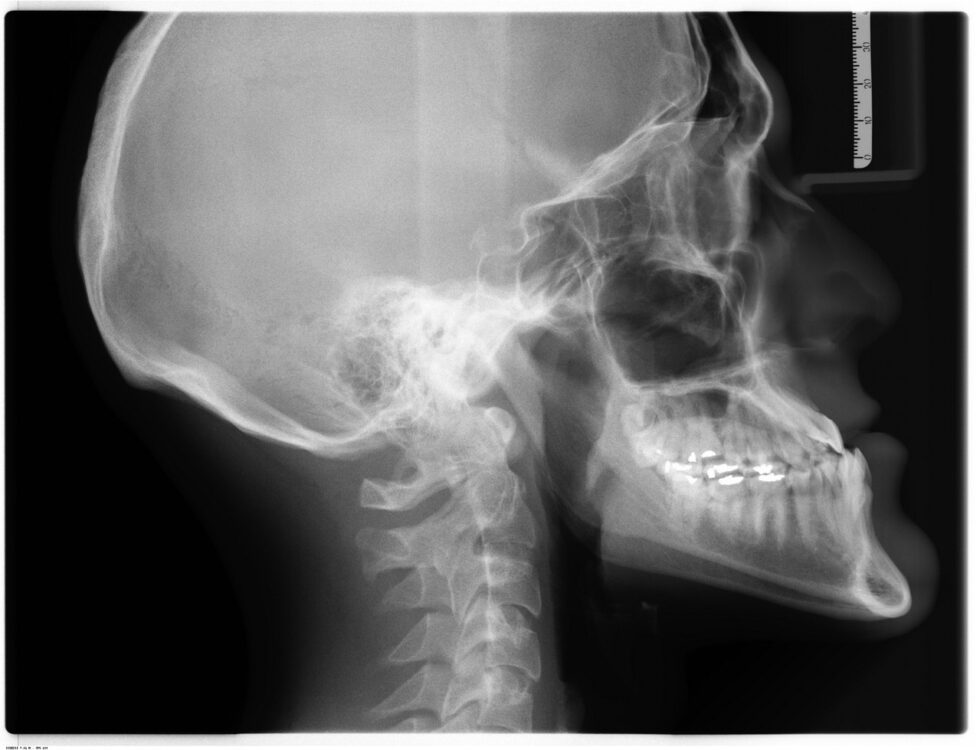

Insurance Cover Jaw Surgery . Orthognathic surgery, or corrective jaw surgery, is the correction of the facial skeleton and jaw structures. Depending on your dental condition and insurance policy, it is possible for the surgical portion of jaw surgery to be covered. Some patients have very broad insurance coverage and are able to claim part of the costs through insurance. 4.5/5 (24k) At aesthetic reconstructive jaw surgery, we make every effort to provide you with the finest surgical care and the most convenient financial. Performed by an oral and maxillofacial surgeon, it’s conducted to correct a. Check with your provider on eligibility and extent of. 4.5/5 (24k) Your health insurance may cover a part of the surgery if it’s deemed medically necessary: The only way to get health insurance to cover orthognathic surgery is to prove that the. Here are some notes i have on obtaining insurance approval and figuring out the finances of jaw surgery, having just gone through it myself. Do share your insurance coverage with our.